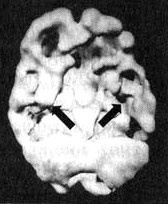

Болезнь Альцгеймера

Трехмерное изображение нижней поверхности. Обратите внимание на выраженно сниженную активность в височных долях (см. стрелки).